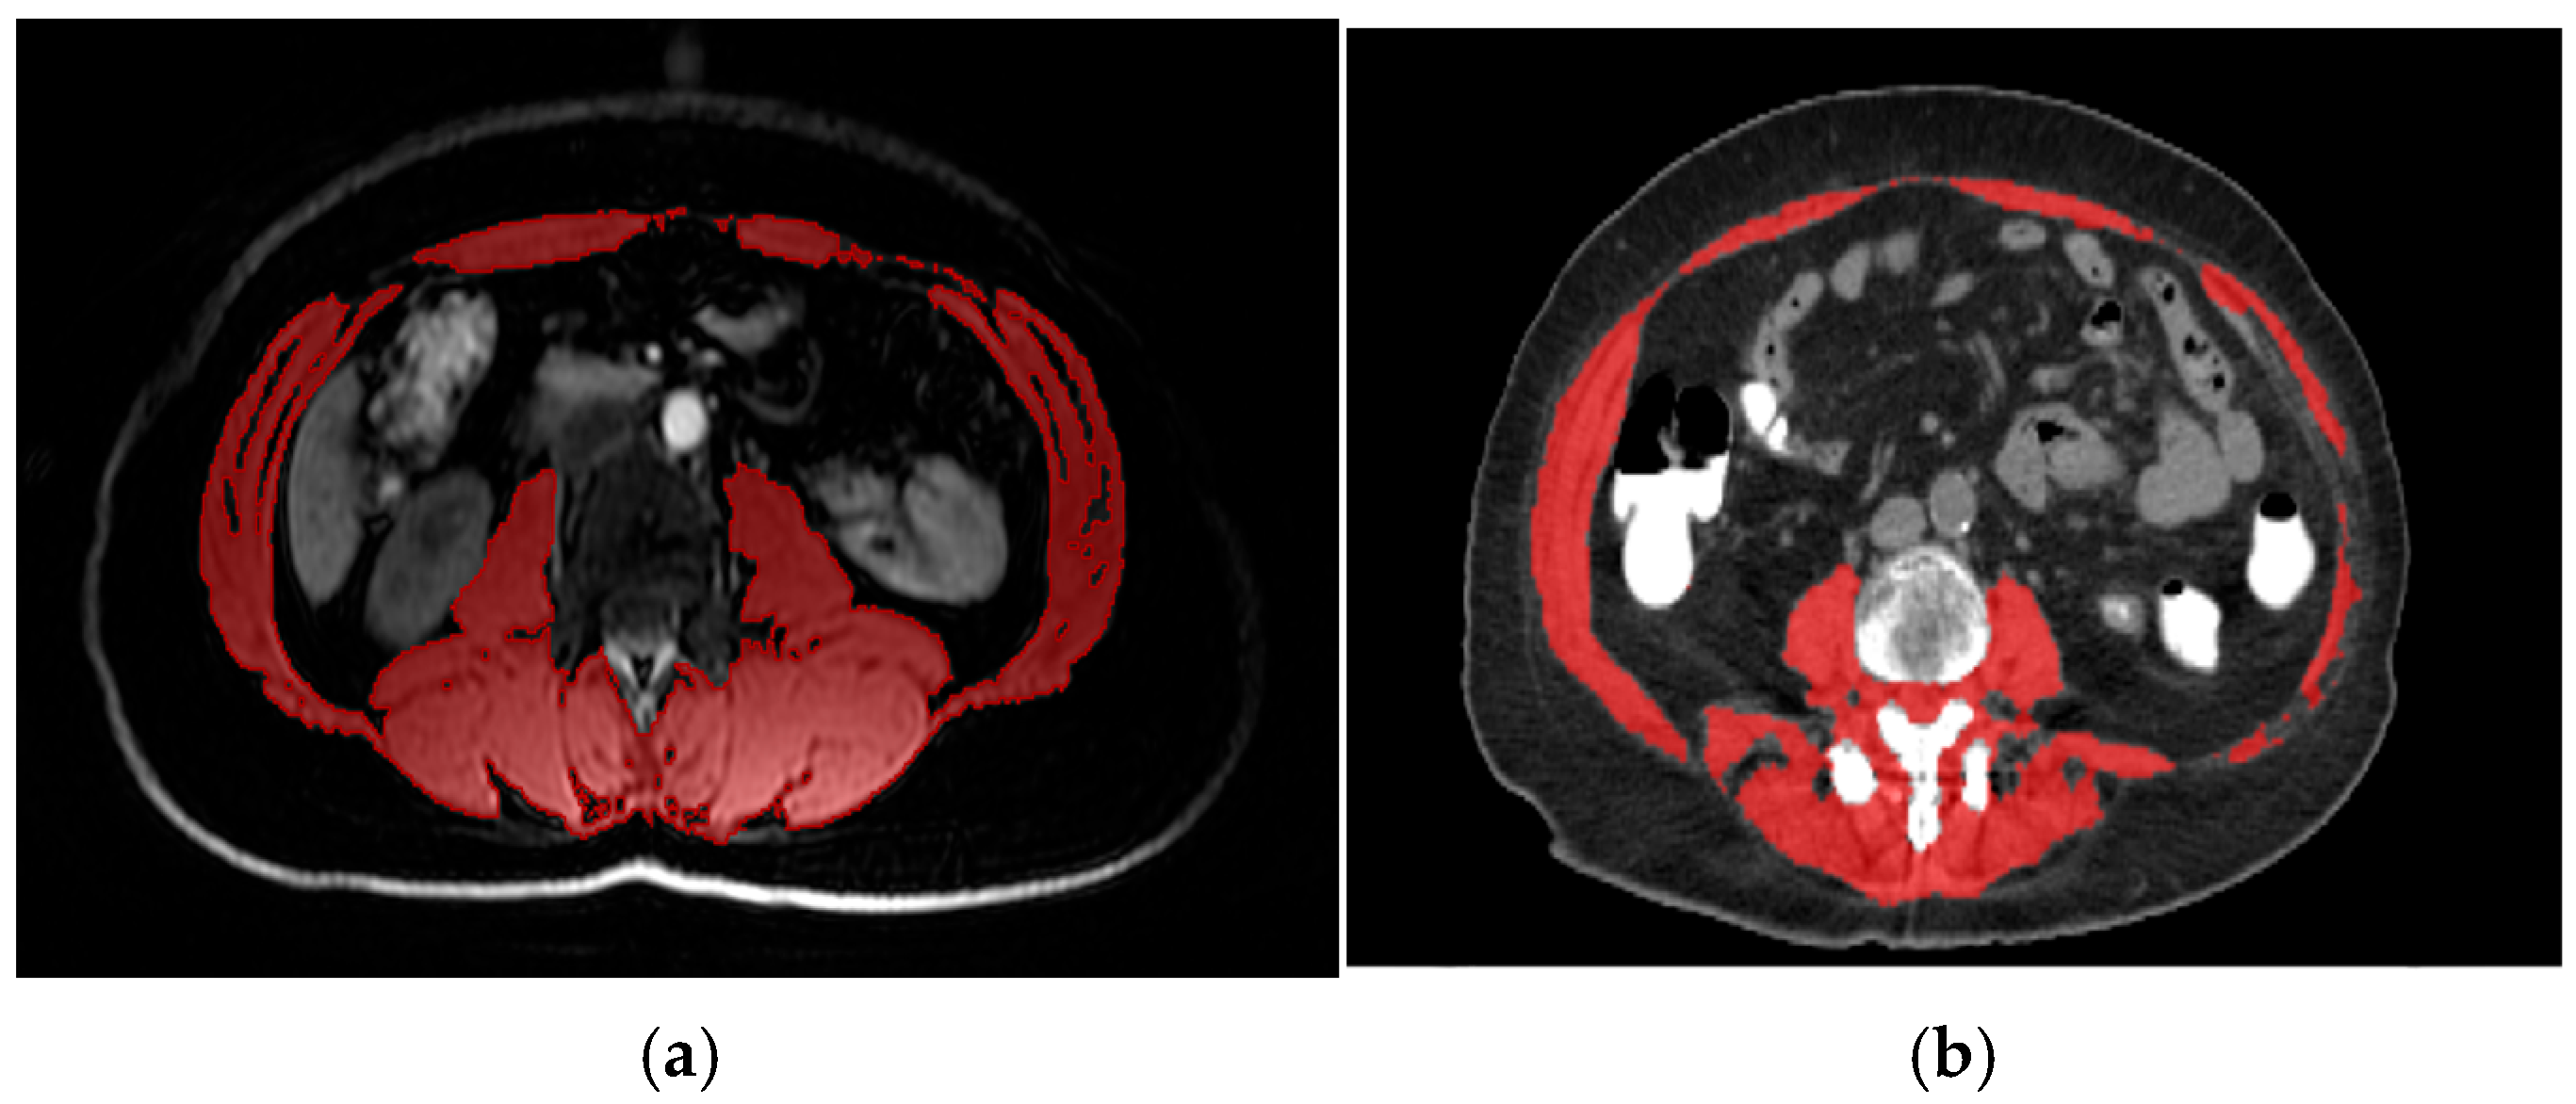

SMI was assessed using PET-CT or PET-MRI images obtained prior to neoadjuvant therapy. It was calculated at the level of the third lumbar vertebra (L3) by dividing the total skeletal muscle area (cm2) by the square of the patient’s height (m2) (Figure 1). To establish an optimal threshold for low SMI, a receiver operating characteristic (ROC) analysis was performed; however, no clearly discriminative cut-off with sufficient sensitivity and specificity was identified. Therefore, a cut-off value of <38.5 cm2/m2 was used to define radiologically defined sarcopenia, in accordance with previously validated criteria for women [12,28].

(a) Axial PET-MRI slice at the L3 vertebra in a patient with triple-negative breast cancer. Skeletal muscle area (red) was manually segmented on T1-weighted, water-only images using 3D Slicer (version 5.7.0; www.slicer.org, accessed on 13 May 2024; The Slicer Community, Brigham and Women’s Hospital, Boston, MA, USA) based on anatomical landmarks and signal intensity. SMI was calculated by dividing the muscle cross-sectional area (cm2) by height squared (m2). (b) Axial PET-CT slice at the L3 vertebra in a patient with triple-negative breast cancer. Skeletal muscle area (red) was segmented using CoreSlicer (version 1.0.0; Montreal, QC, Canada) with predefined Hounsfield unit thresholds (–29 to +150 HU). SMI was calculated as total skeletal muscle area (cm2) divided by height squared (m2). White areas in both images represent contrast enhancement.